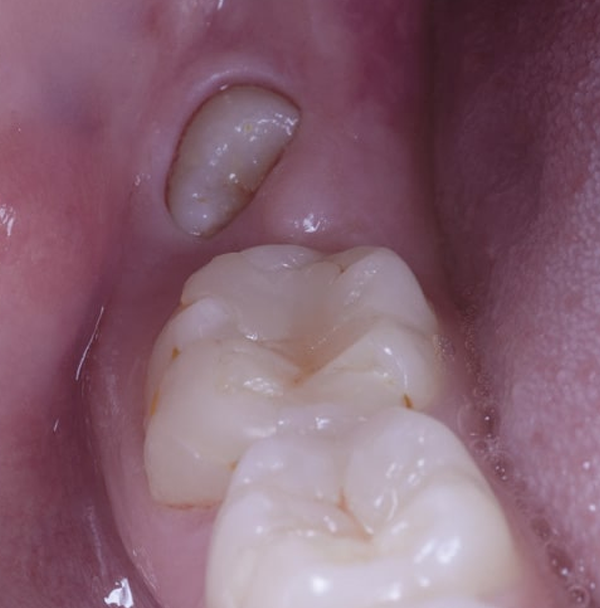

Dolor de muelas del juicio

Los síntomas más frecuentes son:

- Dolor en la zona de muela.

- Inflamación.

- Enrojecimiento.

- Dolor de cabeza.

- Dolor de oído.

- Mal aliento.